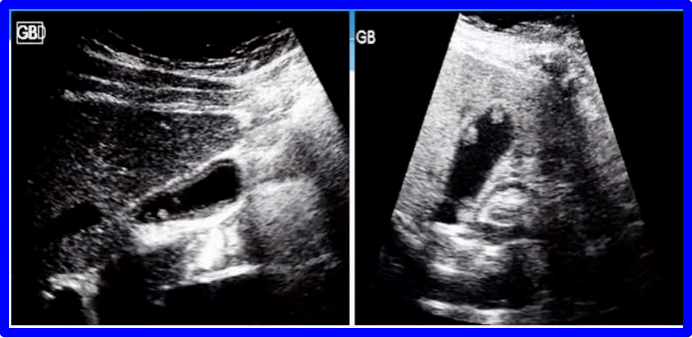

胆囊超声胆囊癌实块型

高手进阶胆囊癌的超声特征

多图文助你熟练掌握胆囊癌超声诊断